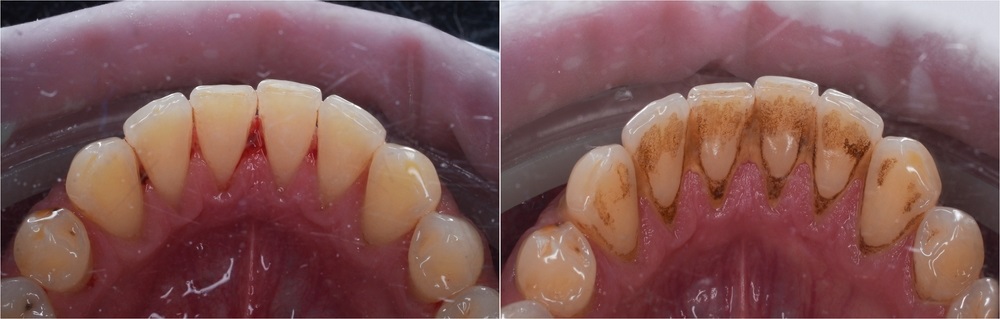

• Cao răng huyết thanh: Cao răng thường nếu không điều trị kịp thời, gây chảy máu nướu, máu ngấm vào mảng bám chuyển thành màu nâu đỏ gọi là cao răng huyết thanh. Cao răng huyết thanh xuất hiện trong khe hở (kẽ) giữa răng và đường viền nướu. Cao răng này thường có màu nâu hoặc răng đen và chứa nhiều vi khuẩn hơn, gây viêm nướu và đẩy nhanh tốc độ nhiễm trùng chân răng.

Cao răng dưới nướu có màu nâu hoặc đen và thường đi cùng tình trạng viêm nha chu.

Cao răng cấp độ 3 dễ dàng nhận ra bởi màu vàng sậm. Các mảng bám thường xuất hiện ở mặt trong của răng, với độ dày và cứng chắc, khiến việc loại bỏ trở nên khó khăn. Trong một số trường hợp, cao răng cấp độ 3 cũng có thể xuất hiện ở mặt ngoài của răng.

Cao răng cấp độ 4 được xem là giai đoạn nghiêm trọng nhất, khi các mảng bám đã chuyển sang màu sậm hơn, thậm chí là màu đen. Ở giai đoạn này, cao răng không chỉ bám chặt mà còn bắt đầu xâm nhập vào chân răng và xương hàm, làm tăng nguy cơ mắc phải nhiều bệnh lý nghiêm trọng về răng miệng.